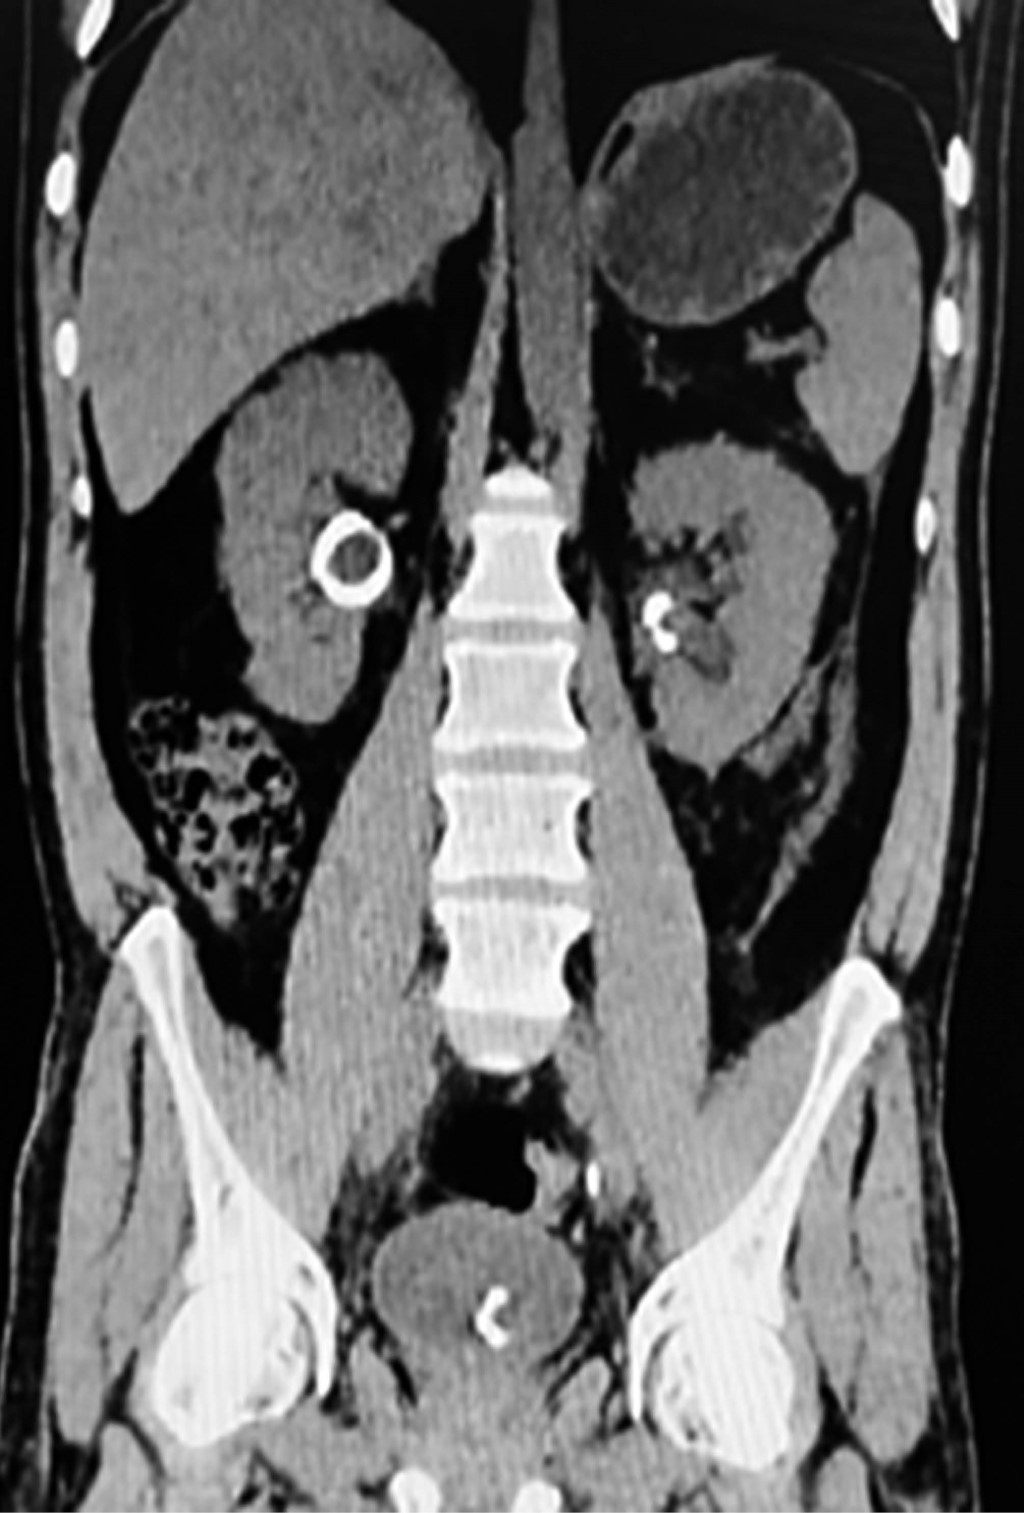

Figure 1